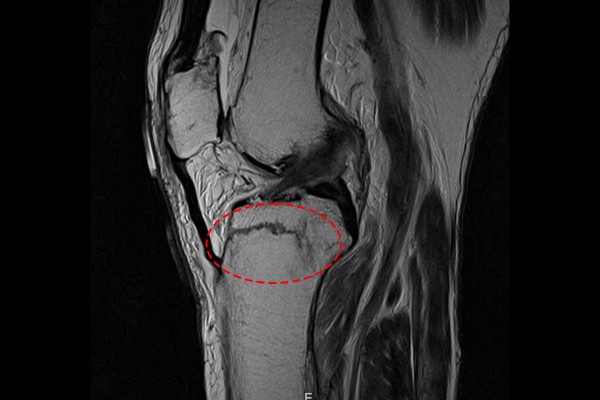

환자분께서는 내원해주실 때 타병원에서 촬영하신 MRI를 지참해오셨습니다. MRI 사진을 확인해보니 증상을 호소하신 무릎 경골 고평부에서 명확한 골절 확인되었습니다.

2f992d7239a97edca630fa072198310c_1766717638_0021.jpg

측면 MRI 사진에서 역시 명확하게 골절선이 확인되어 무릎 경골 고평부 골절(Fx. tibia plateau knee Rt.[Schatzker 4 or 5])을 진단하였습니다.